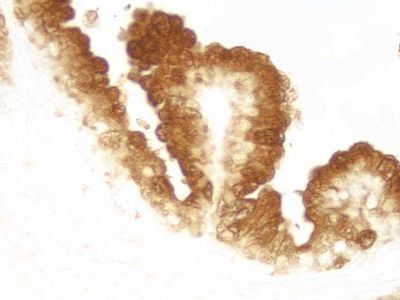

?The ImmPRESS polymerized reporter enzyme staining system uses novel conjugation and micropolymer chemistries to create a highly sensitive, ready-to-use, one-step, non-biotin detection system for immunohistochemistry and immunocytochemistry staining. This unique micropolymer of highly active horseradish?peroxidase (HRP)?is attached to our affinity purified secondary antibodies, producing reagents with outstanding sensitivity and low background.

The peroxidase micropolymers of the ImmPRESS HRP polymer reagent limit steric interference and provide enhanced accessibility to the target, avoiding the disadvantages of other polymer systems that use large dextrans or other macromolecules as backbones. The result is crisp, strong staining of antibody targets, especially nuclear and membrane antigens (such as Ki67, estrogen receptor, bcl-2, CD3, CD8 and CD10) and greater sensitivity than other polymer systems.

The staining procedure is simple as shown in the diagram below. Following a blocking step with the diluted normal horse serum, sections are incubated with primary antibody. After a brief wash, the appropriate ImmPRESS Reagent is added to the sections and incubated for 30 minutes. Sections are again rinsed and the slides are developed with the peroxidase substrate of choice.